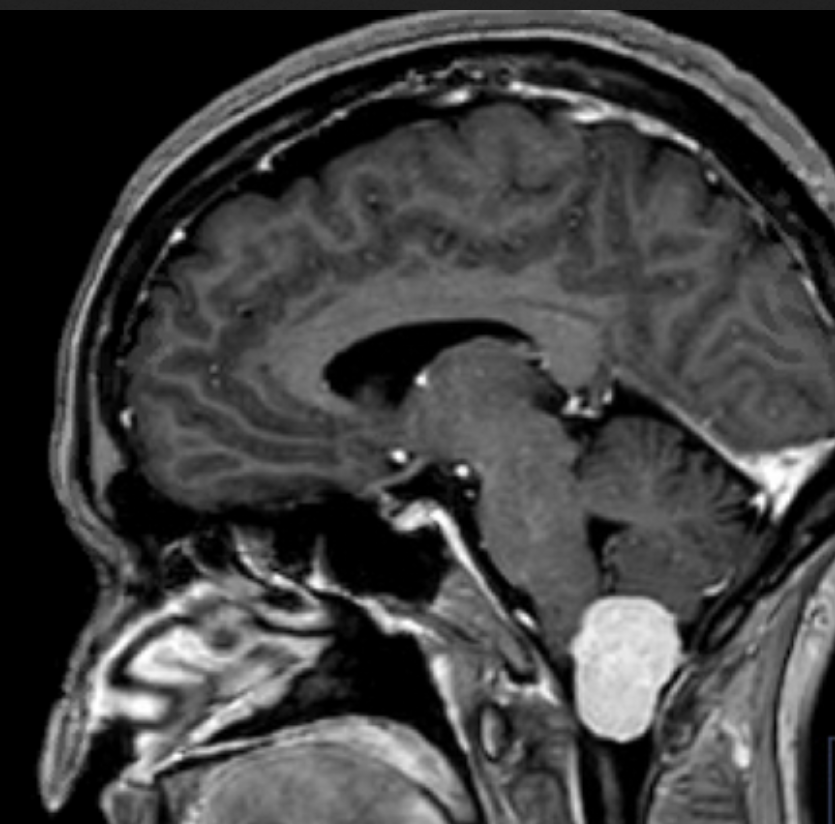

I just pulled this random brain MRI image off the web, uploaded it to Grok and said "analyze this." Here's what Grok came back with:

The image you’ve provided appears to be a sagittal (side view) magnetic resonance imaging (MRI) scan of a human brain. Here’s a detailed analysis based on the visual characteristics:

- Type of Scan: This is an MRI, likely a T1-weighted or T2-weighted image, given the contrast and grayscale appearance typical of brain MRIs. The scan shows detailed anatomical structures of the brain, including the cerebral cortex, cerebellum, brainstem, and spinal cord.

- Orientation: The image is in the sagittal plane, providing a side view of the brain and upper spinal cord, slicing through the midline of the head.

- Quality: The image is clear, with good resolution, allowing for the identification of major brain structures and potential abnormalities.

- Cerebral Cortex: The outer layer of the brain, with its characteristic folds (gyri) and grooves (sulci), is visible at the top of the image. The gray matter of the cortex contrasts with the underlying white matter.

- Cerebellum: Located at the lower back part of the brain, the cerebellum is visible with its folded structure, responsible for coordination and balance.

- Brainstem: The brainstem, connecting the brain to the spinal cord, is seen extending downward from the cerebellum. It includes structures like the midbrain, pons, and medulla oblongata.

- Spinal Cord: The upper portion of the spinal cord is visible at the bottom of the image, extending downward from the brainstem.

- Ventricles: The lateral and third ventricles, part of the brain’s fluid-filled system, are faintly visible as darker areas within the brain tissue, though they’re not as prominent in this sagittal view as they would be in a coronal or axial slice.

- Pituitary Gland: A small, rounded structure near the base of the brain, just above the brainstem, is likely the pituitary gland, which regulates hormones.

- White Spot at the Base of the Brain: There appears to be a bright, rounded spot near the base of the brain, close to the pituitary gland or hypothalamus region. This could represent a variety of things, such as:

- A benign cyst or lesion (e.g., a pineal cyst, which is common and often harmless).

- A calcification or artifact (bright areas on MRI can sometimes be due to imaging artifacts or contrast agents).

- A tumor or other pathology, though this would require further evaluation by a radiologist or neurologist to determine its nature (benign or malignant, size, etc.).

- Symmetry and Structure: The brain appears generally symmetrical, with no obvious large-scale asymmetry or significant structural deformities visible in this single slice. However, a full assessment would require multiple planes (axial, coronal) and possibly additional imaging sequences (e.g., FLAIR, diffusion-weighted imaging).

- No obvious signs of major trauma, bleeding, or large masses: There are no visible signs of large hemorrhages, significant edema (swelling), or obvious tumors based on this single image. However, small or subtle abnormalities might not be detectable without additional context or scans.